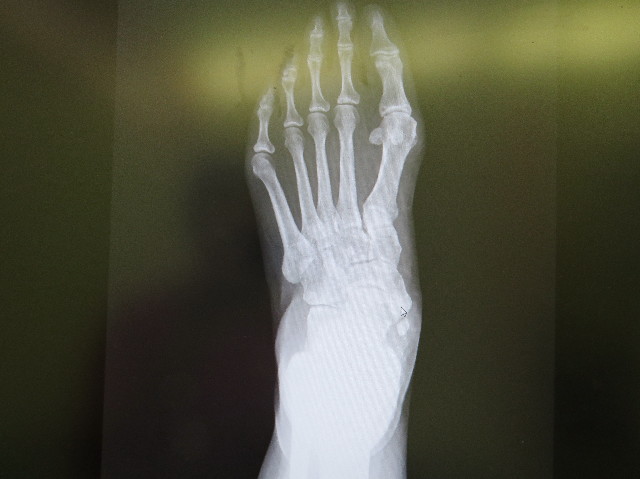

これ(下の画像)は前の先生のところで撮ったレントゲンですが

こんなに大きな『石灰化』は初めて見たと助手の先生がおっしゃっていました。

持参したMRI画像をみたところでは、外脛骨周辺だけでなく、腱やスジの炎症がかなりあって、この炎症のせいで痛いのでしょうとのこと。

(炎症部分が長く大きくあちこち真っ白に写っていてよくわかります)